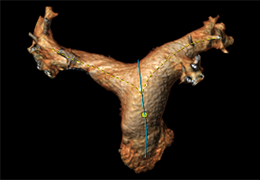

High-quality and fast 3D reconstruction and 3D rendering

Performs 3D reconstruction and volume rendering.

Instant and interactive surface extraction and export to STL and PLY formats.